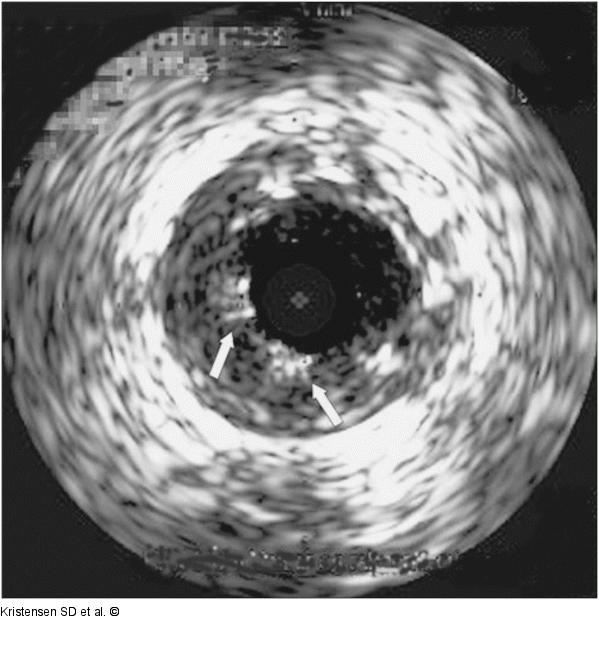

Abbildung 3: LAD Intravascular ultrasound scan of the LAD showing stent malapposition (arrows) at the time of very late ST. |

Intravascular ultrasound scan of the LAD showing stent malapposition (arrows) at the time of very late ST. |